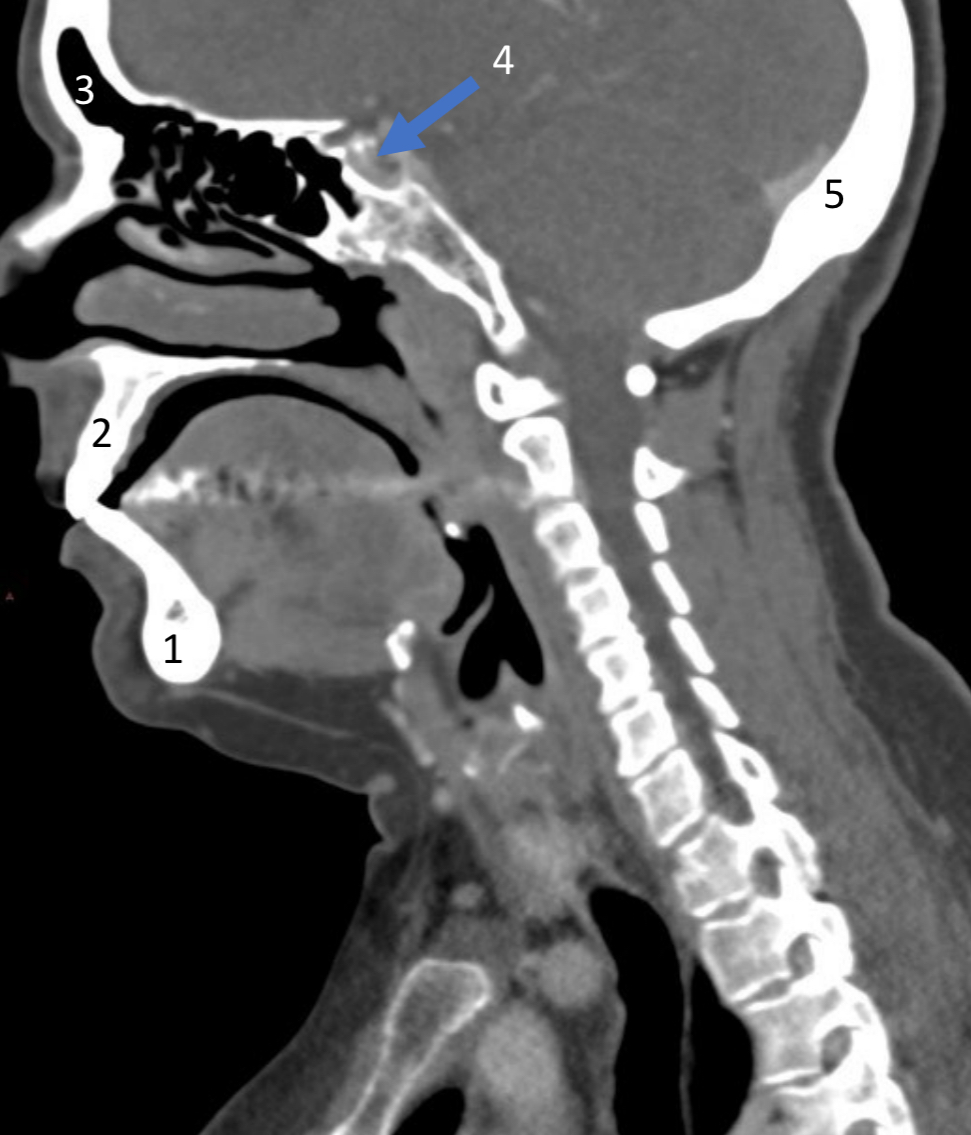

Mandible

ID bone

Maxilla

ID bone

Frontal sinus

ID structure

Pituitary fossa

ID structure

Occipital

ID bone

Lambdoid suture

ID structure

Frontal sinus

ID structure

Orbital margin

Orbit

Maxillary sinus

ID structure

Mandibular condyle

ID structure

Inferior nasal concha

ID structure

Hard palate

ID strucutre

Gonial angle

ID strucutre

Petrous ridge

ID structure

Groove of middle meningeal a.

ID structure

Roof of orbit

ID structure

Frontal sinus

ID structure

Pituitary fossa

ID structure

Petrous ridge

ID structure

Sphenoid sinus

ID structure

Hard palate

ID structure

Mastoid air cells

ID structure